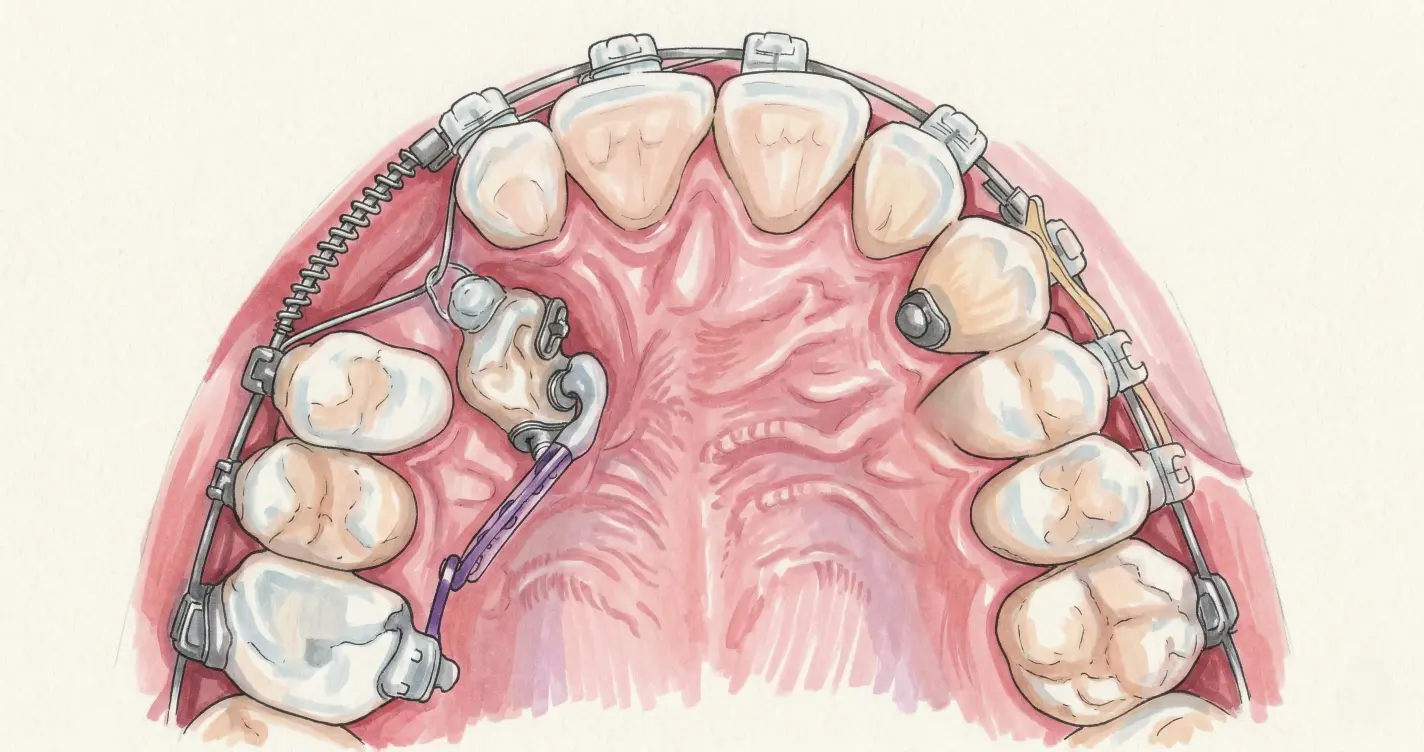

Как происходит ортодонтическое вытяжение

- Создание места. Брекет-системой освобождают пространство в зубном ряду — 3–6 месяцев.

- Хирургическое обнажение. Хирург делает разрез десны, при необходимости убирает небольшой фрагмент кости и обнажает коронку зуба. На неё приклеивается металлическая кнопка или брекет.

- Вытяжение. К кнопке подвязывается эластичная цепочка, соединённая с дугой брекет-системы. Постоянное небольшое усилие тянет зуб — миллиметр за миллиметром. Согласно систематическому обзору Mousa et al (2022), разные методы тракции (8) дают сопоставимые результаты — важнее своевременность начала. Mousa et al., 2022

- Финальное выравнивание. Когда зуб вышел в ряд, кнопку заменяют на полноценный брекет и завершают лечение стандартно.

Сроки: от 1 до 2 лет в зависимости от начального положения зуба. Процедура безболезненна.